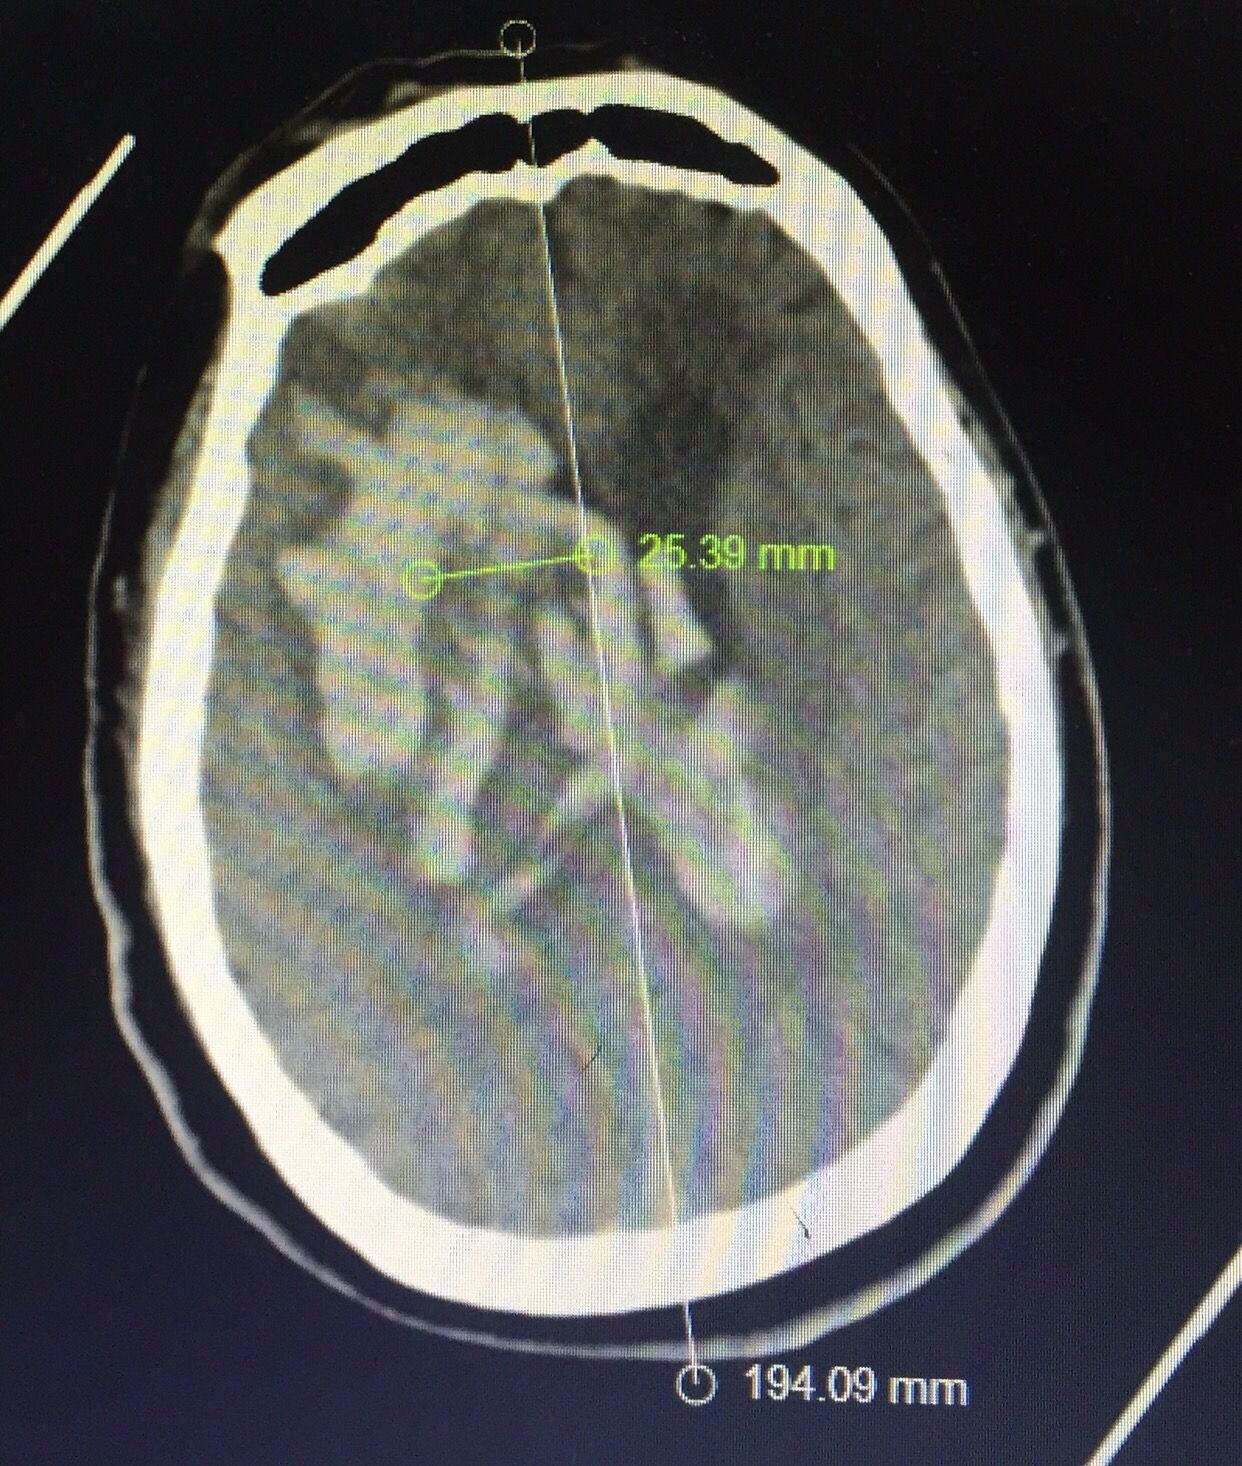

CT片见上图:

右侧基底节出血破入脑室脑积水

认真阅片可知,血肿最大层面就是脑室额角层面,EVD的靶点就是额角室间孔位置,我们把血肿靶点也定在这一层,右侧血肿内,右侧额角室间孔位置偏右,如图↑↑

经kocher点穿刺定位画线↑↑

中线旁开2.5㎝平行矢状线穿刺右侧血肿;偏内穿左侧脑室